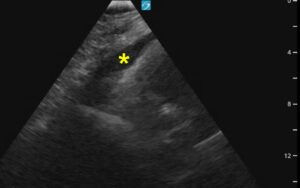

GORE_Figure1